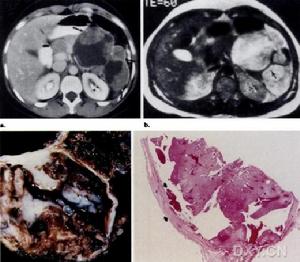

肺囊性纖維化病理 粘稠分泌物阻塞胰腺外分泌管,早期出現胰管擴張、腺泡擴大形成囊腫,繼以廣泛纖維化伴細胞浸潤、萎縮,引起糖尿病。外胰腺管阻塞,胰腺酶包括胰蛋白酶、脂肪酶和澱粉酶的分泌不足或缺乏,導致消化、特別是脂肪吸收不良。

肝臟內小膽管被粘液堵塞,引起多小葉性肝硬化、門靜脈高壓和肝功能損害,並可並發脾功能亢進。膽道阻塞可引起黃疸。膽汁缺乏對脂類的消化、脂溶性維生素的吸收、胰液和腸液的消化作用以及腸蠕動都有不良影響。粘液可使腸道上皮剝脫,結構破壞。新生兒在迴腸末端發生胎糞梗阻,為早期常見表現。汗腺分泌中氯化鈉含量明顯增高。輸精管發生纖維化阻塞,失去生育能力。女性生殖能力減退。